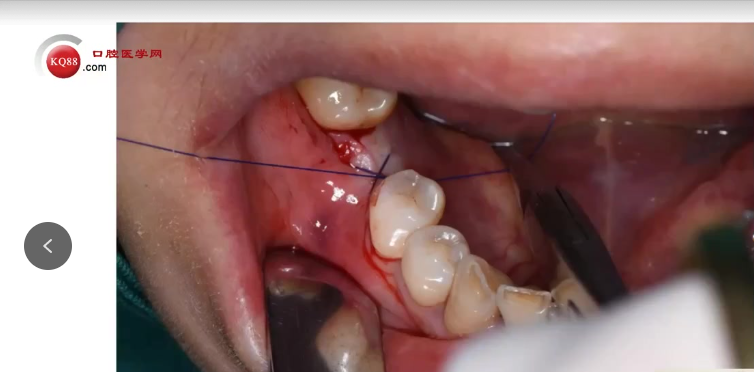

愈合方式选择:根据骨质与稳定性,放置覆盖螺丝或愈合基台,缝合创口。

切记:初期稳定性不足时,应选择埋入式愈合,延长愈合时间至6个月以上,避免微动导致失败。